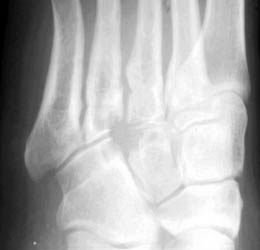

26 years old female presenting with painful soft tissue mass at the plantar aspect of the left foot.MR demonstrates this mass is isointense on T1,isointense to minimally hyperintense on proton density and hyperintense on T2 W and Stir images. Bony erosions are identified in 3rd cuneiform, cuboid and bases of 3rd and 4th metatarsals on MRI and plain radiographs.Few foci of low signal intensity hemosiderine deposits are identified on all pulse sequences.